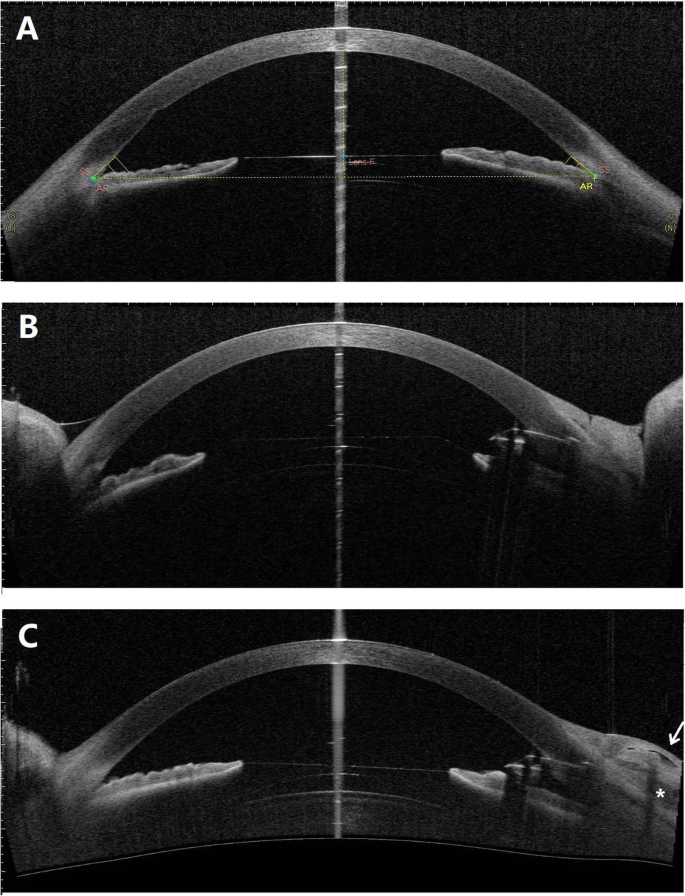

Anterior segment OCT images of the right eye. a The well-placed ICL and narrow trabecular-iris angles on presentation. b The slightly shallow anterior chamber with ICL tilting towards the cornea 2 days after Ex-PRESS shunt implantation. c The well-placed ICL and Ex-PRESS shunt with a well-functioning bleb 1 month after surgery. The internal fluid-filled cavity (white arrow) and hyporeflective area (*) are noted in the bleb

The ICL position and anterior chamber angles were carefully assessed with anterior segment OCT (CASIA, Tomey Corp., Nagoya, Japan). ICLs were well placed with vault heights of 456 µm and 629 µm in the right (Fig. 2a) and left eyes, respectively. The trabecular-iris angles at 500 µm from the scleral spur (TIA500) ranged from 13.5 degrees to 25.2 degrees in all quadrants of both eyes. The angle opening distance at 500 µm from the scleral spur (AOD500) was 0.27 mm and 0.22 mm in the superior quadrant of the right and left eyes, respectively. Gonioscopy showed that the angles were open but narrow (Shaffer grade II-III) with mild to moderate trabecular pigmentation in both eyes (Fig. 3a, b).

On postoperative day 1, the BCVA was 20/60, and the IOP was 6 mmHg. Slit lamp examination revealed a slightly shallow anterior chamber compared with the left eye (Fig. 1b). The ICL appeared to tilt towards the cornea and against the pupil margin (Figs. 1b and 2b). The ICL vault height was 431 µm based on measurements with anterior segment OCT on postoperative day 2. The IOP increased to 9 mmHg, and the anterior chamber depth increased after one week. One month after surgery, the BCVA was 20/50, and the IOP was 12 mmHg. The ICL returned to a well-placed position with a vault height of 451 µm (Fig. 2c). A functioning bleb with an internal fluid-filled cavity and hyporeflective area was noted by anterior segment OCT imaging. During the 3-month follow-up, the IOP remained stable at 12 ~ 14 mmHg, and the Ex-PRESS shunt was well positioned with a diffuse and avascular bleb (Fig. 1c).

Ex-PRESS shunt implantation is typically not recommended for angle-closure glaucoma treatment due to the narrow peripheral anterior chamber. In myopic eyes with ICL implantation, the peripheral anterior chamber is commonly narrower than its natural status. We carefully assessed the peripheral anterior chamber parameters preoperatively. The AOD500 was 0.27 mm in the superior quadrant of the right eye, whereas the average external diameter of the Ex-PRESS P50 tube was 0.38 mm [21]. The peripheral anterior chamber would not be wide enough to accommodate the Ex-PRESS tube if the device was inserted through the blue-grey transition zone, which corresponds to the location of the trabecular meshwork. Hence, we chose the front edge of the blue-grey transition zone as the penetration site that would allow more space to accommodate the Ex-PRESS tube. Postoperative anterior segment OCT imaging confirmed the suitable Ex-PRESS position without contact with either the iris or the cornea (Fig. 2c). Over a long run, the peripheral anterior chamber may progressively narrow due to the age-related lens thickening (cataract formation). In that case, a laser iridoplasty around the shunt may help resolve the mechanical contact between the Ex-PRESS and the iris [23]. In cases with significant cataract formation, ICL explantation and cataract surgery would substantially deepen the peripheral anterior chamber.